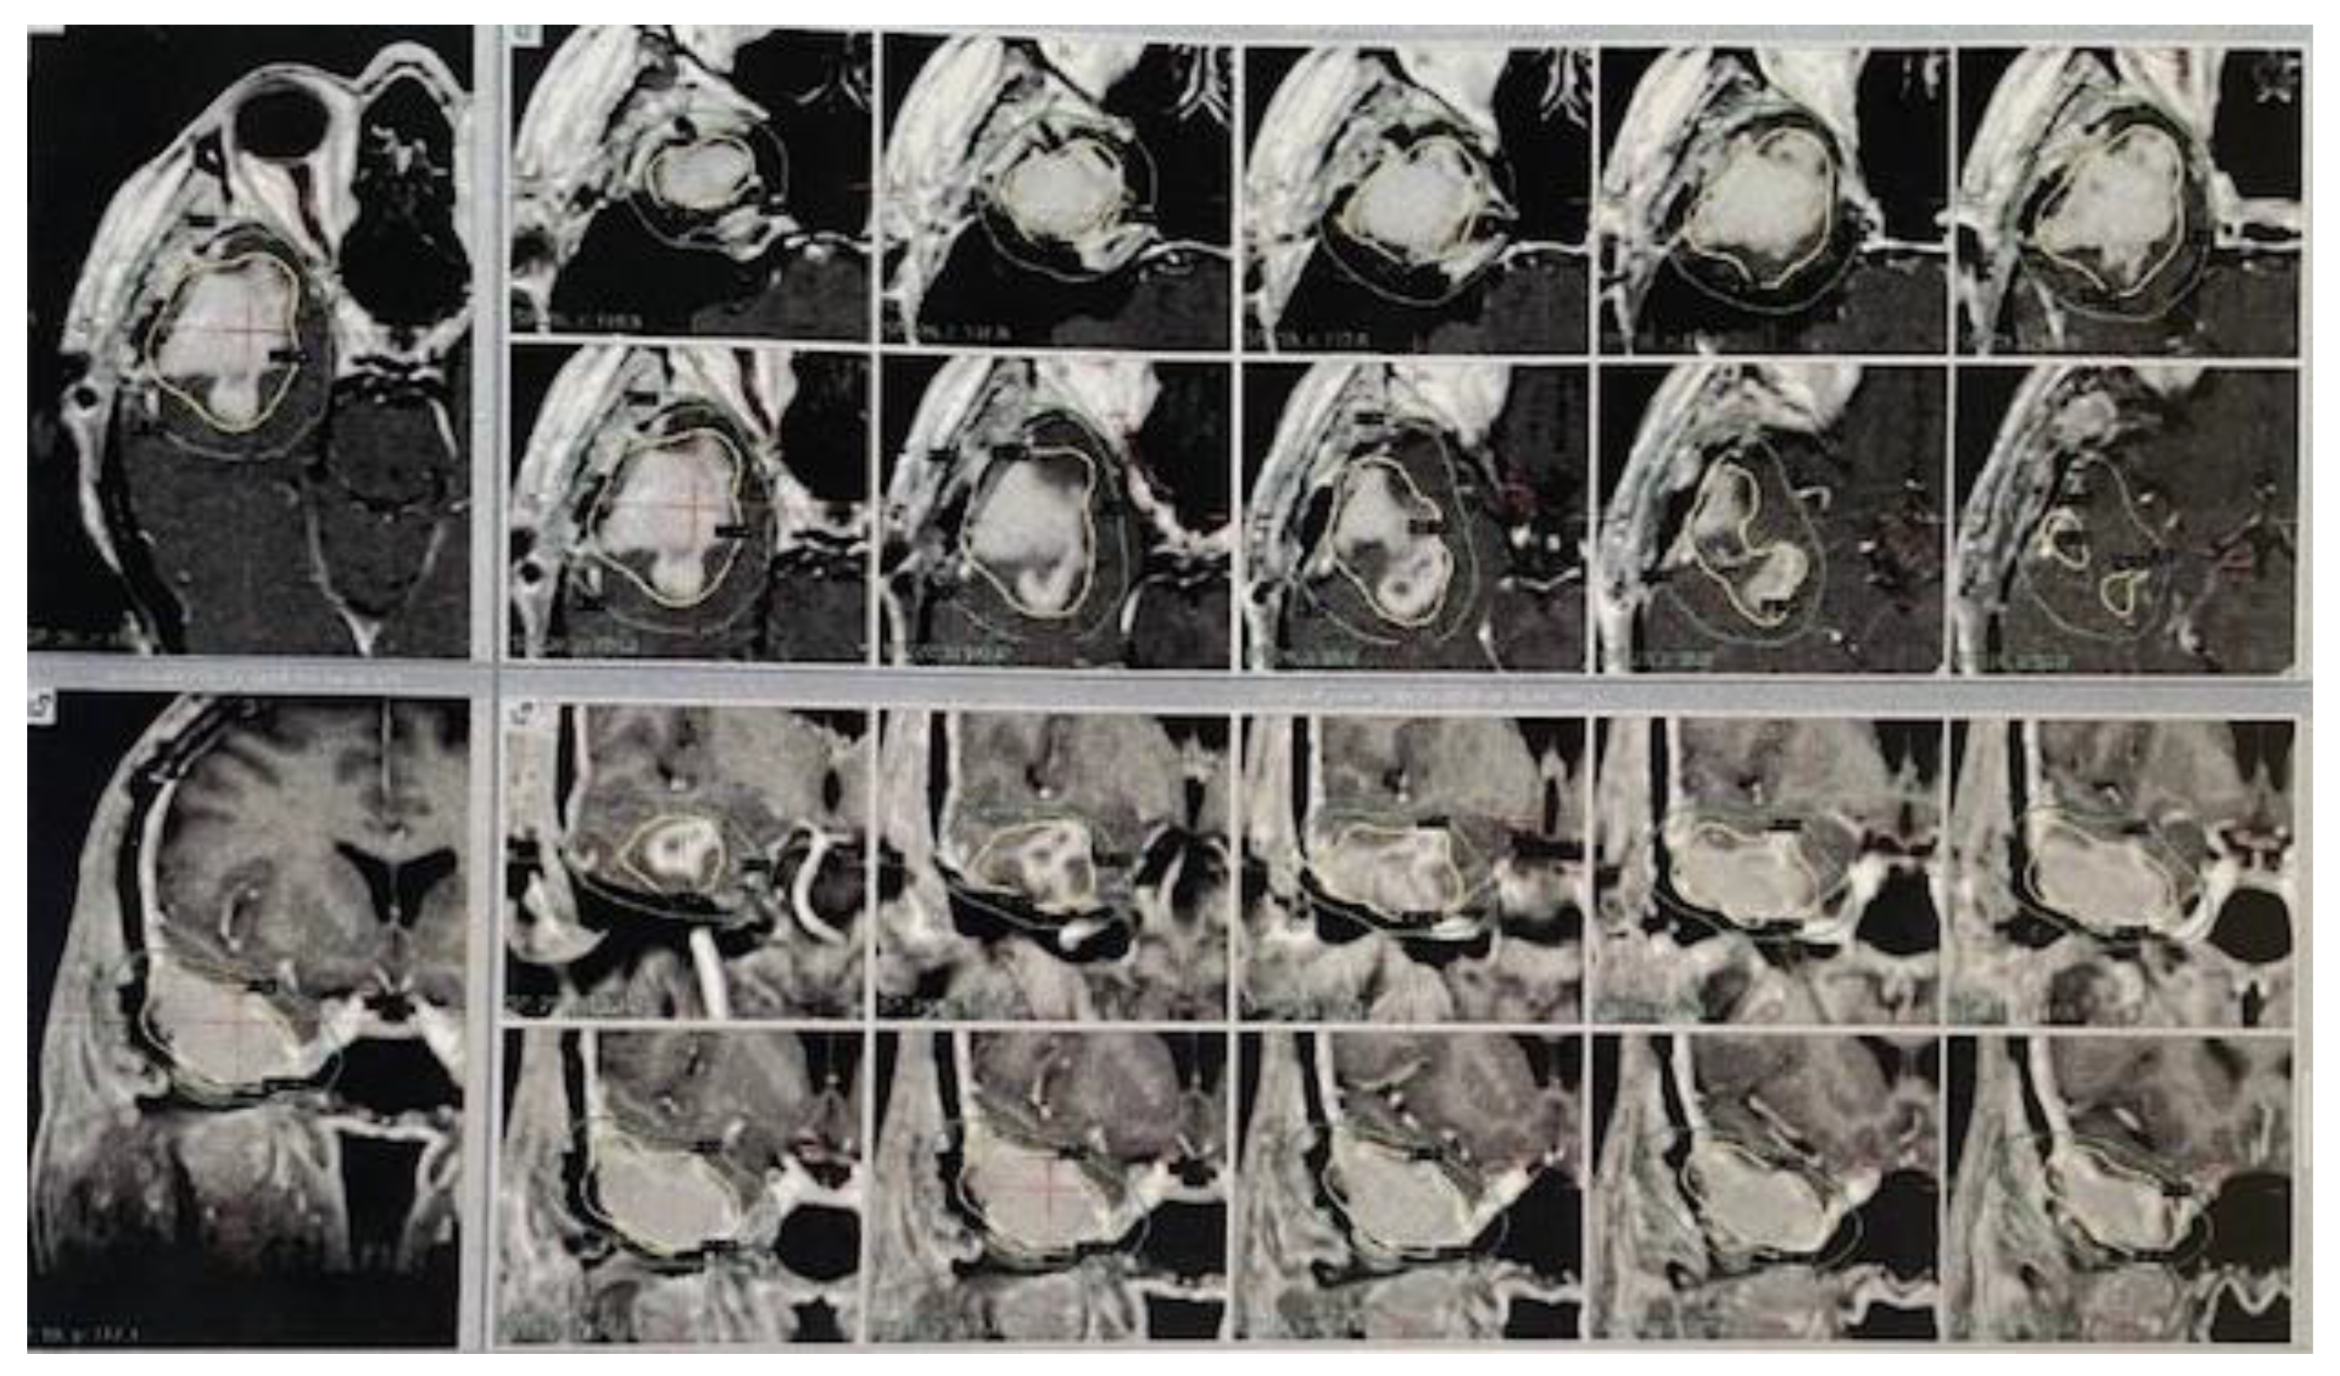

3.2. Gamma Knife Radiosurgery Characteristics

- Valerio, J.E.; Wolf, A.; Wu, X.; Santiago Rea, N.; Fernandez Gomez, M.; Borro, M.; Alvarez-Pinzon, A.M. Assessment of Gamma Knife Stereotactic Radiosurgery as an Adjuvant Therapy in First-Line Management of Newly Diagnosed Glioblastoma: Insights from Ten Years at a Neuroscience Center. Int. J. Transl. Med. 2024, 4, 298–308. [Google Scholar] [CrossRef]